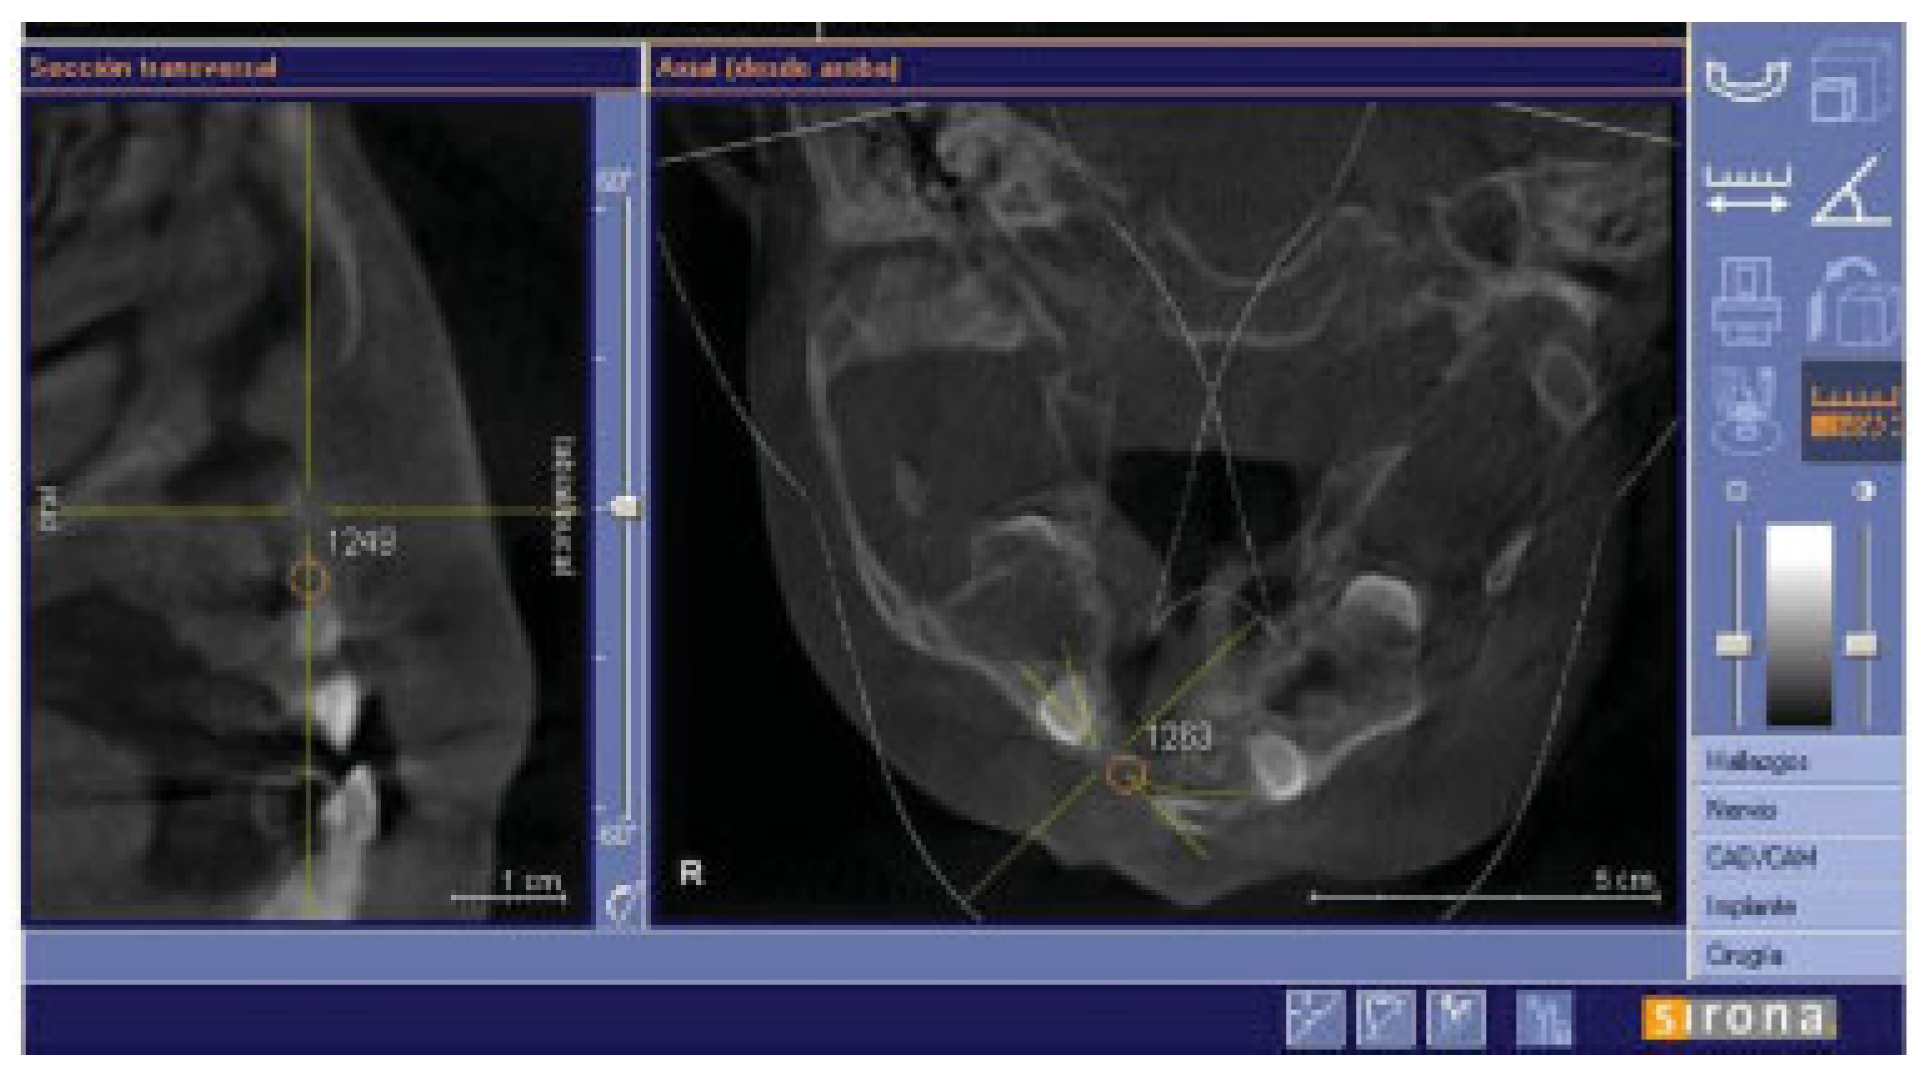

There were no intraoperative or postoperative complications. The fissure length in the upper edge when measured with a rule tool in the CBCT with Sirona Galileos software range from 5.76 to 16.93 mm (mean, 11.18 mm) (►Figure 4). All patients in the DBM group underwent a second CBCT assessment after 6 months of the surgical procedure. In the axial, coronal, and sagittal views and the three-dimensional reconstruction, there was no bone formation in none of the patients. The highest grayscale value in the area of the cleft was registered (►Figure 5), finding gray values between 1,148 and 1,496 (mean, 1,278.15). In our patients, the gray values corresponding to the bone adjacent to the cleft were higher than 1,504. During the follow-up performed 15 to 33 months postoperatively (mean, 28.2 months), occlusal and periapical X-ray were performed and analyzed by applying the Enemark scale; satisfying bone formation of 75% was observed only in just one patient. Four patients were reoperated with conventional surgery, using iliac crest grafts, because they need orthognathic surgery with Le Fort I osteotomy. At the time of reoperation, no bone formation was observed, although a crystallized material was seen in the pocket (►Figure 6) and was removed.

Figure 5.

Sagittal and axial slides to show gray values at the alveolar cleft.